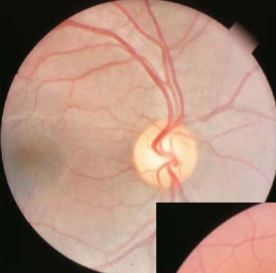

persistent hyaloid artery